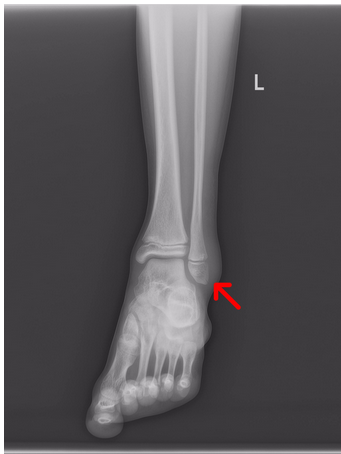

外踝很容易在外力创伤或不适当的运动扭伤踝关节等因素而引起骨折。根据骨折的程度可以选择适当的治疗。

踝骨骨折如果无移位,可以用石膏或夹板固定踝关节。有移位骨折需手法复位后再做外固定。固定期一般在3个月左右。